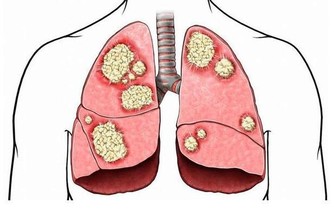

4、抗癌、延年益壽

芝麻是富硒食物,因此它還有良好的抗癌作用;

黑芝麻含有的脂肪大多為不飽和脂肪酸,有延年益壽的作用。